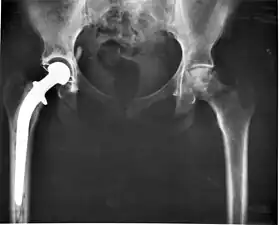

Hip

Hip replacement can be performed as a total replacement or a hemi (half) replacement. A total hip replacement consists of replacing both the acetabulum and the femoral head while hemiarthroplasty generally only replaces the femoral head. Hip replacement is currently the most common orthopaedic operation, though patient satisfaction short- and long-term varies widely.

In recent decades, the most successful and common form of arthroplasty is the surgical replacement of a joint or joint surface with a prosthesis. For example, a hip joint that is affected by osteoarthritis may be replaced entirely (total hip arthroplasty) with a prosthetic hip. This procedure involves replacing both the acetabulum (hip socket) and the head and neck of the femur. The purpose of doing this surgery is to relieve pain, to restore range of motion and to improve walking ability, leading to the improvement of muscle strength.